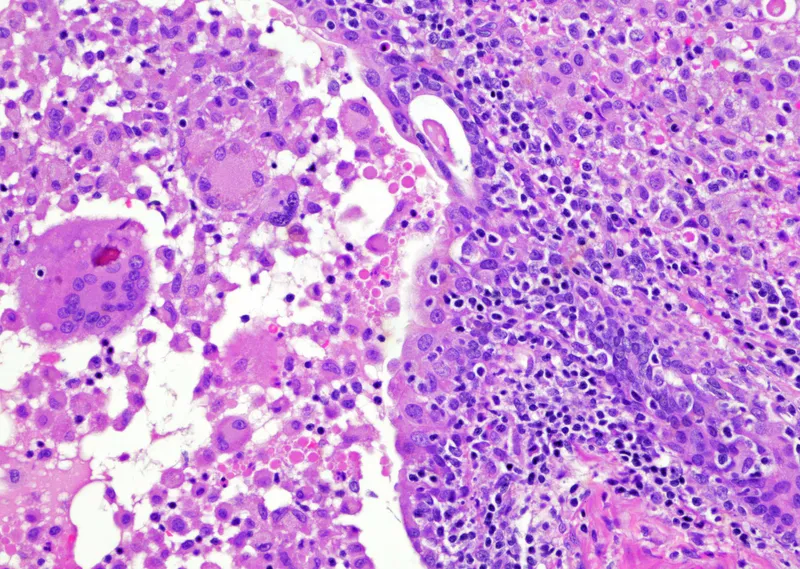

| Granulomatous | Post-BCG therapy, post-TURP, fungal, idiopathic | Variable; may mimic carcinoma | Epithelioid granulomas, giant cells, lymphocytes |

- Histopathology: Perineural invasion is a common finding and hallmark of malignancy.